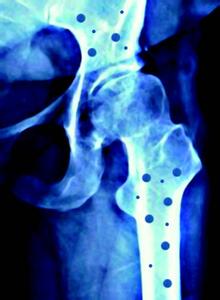

人体正常的骨代谢过程是骨组织不断进行改建活动的一个复杂的过程,包括骨吸收和骨形成两个方面。该过程的顺序一般认为是:激活——骨吸收——骨形成。首先,参与骨吸收的破骨细胞大量被激活,破骨细胞将骨基质溶解,并把骨中的钙移出,形成骨吸收;随后在骨吸收的表面排列成骨细胞,成骨细胞合成非矿化的骨基质,同时把钙运至钙化区;最后,钙、磷结晶逐渐沉积在骨基质中,骨基质钙化,形成骨组织。在骨的代谢过程中,每天都有一定量的骨组织被吸收,又有相当数量的骨组织合成,两者保持着动态的平衡。当骨吸收大于骨质形成,可出现骨丢失、发生骨质疏松症、骨软化病等症。当骨形成而无相应的骨吸收时,则可出现骨质硬化。

骨的代谢过程受到体内许多因素的调节,钙、磷、镁、内分泌激素、维生素等多种因素均起着至关重要的作用。当这些因素的代谢发生异常时,就可造成骨代谢的紊乱。